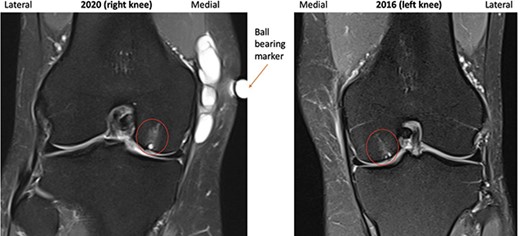

A repeat MRI was performed and reported ‘very similar’ appearances to the left knee, showing a septated ganglion originating from the postero-medial aspect of the joint and subchondral cyst formation with a pattern and location mirroring that which had involved the left knee (Figs 1–3). Reassured by these findings, the patient deferred surgery.

2016 and 2020 T2-weighted MRI in coronal plane with subchondral cyst circled medially.

Subchondral cyst formation associated with localized articular cartilage loss was evident in the weight-bearing portions of both medial femoral condyles and patellae, parts of the knee which are most commonly affected by articular cartilage loss in OA [6].